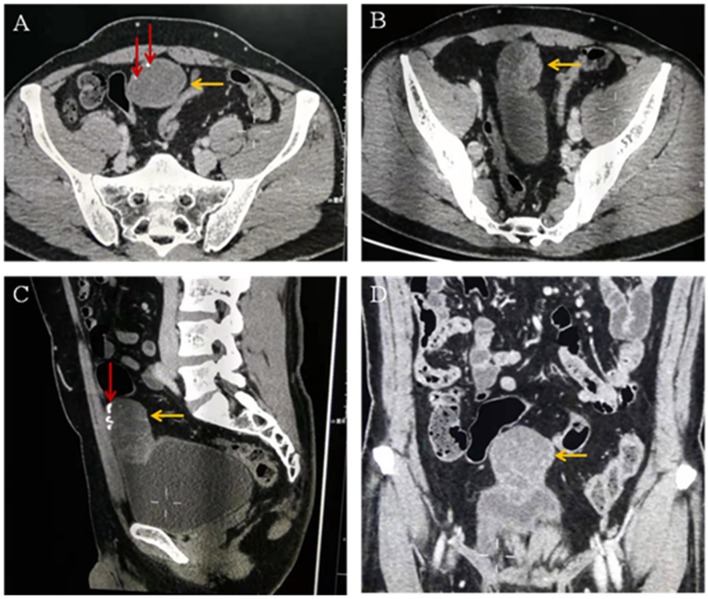

The diagnosis on contrast-enhanced abdominopelvic CT was also umbilical tumor. CT confirmed that there was an intra-abdominal mass with calcification, invasion of the adjacent bladder dome and peritoneum, and which underwent significant enhancement (Figure 2).

Figure 2.

(A–C) Computed tomographic images showing a cystic solid mass (yellow arrow) in the anterior part of the bladder measuring 6.8 × 3.9 cm in size. The tumor invades the anterior wall and peritoneum of the adjacent bladder. Calcification (red arrow) and separation (yellow arrow) are visible within the tumor. (D) Enhanced computed tomographic image showing that the solid part of the mass is obviously enhanced (yellow arrow).